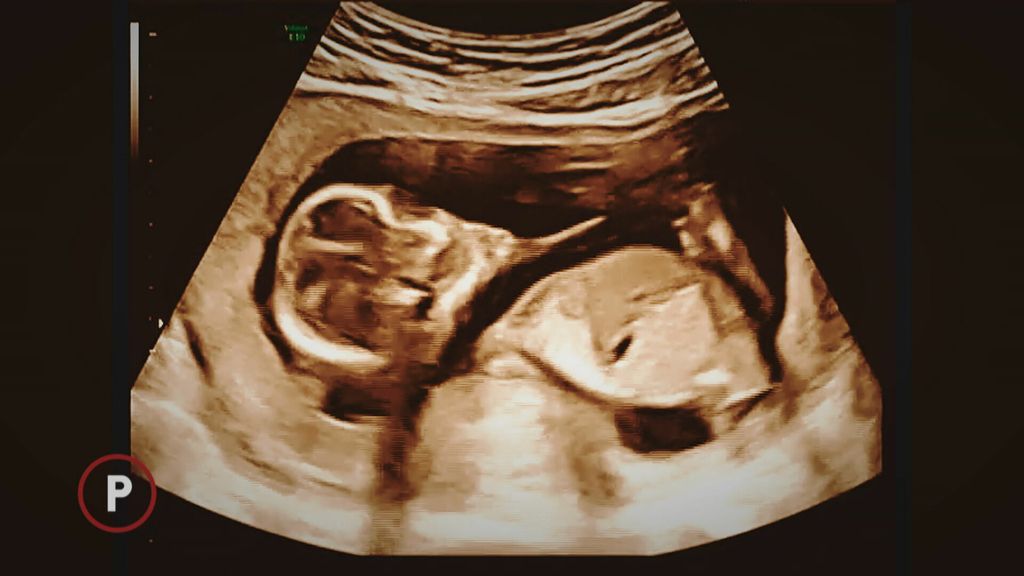

Problemi s trudnoćom uočeni su u 19. tjednu. Sljedećih deset pretvorilo se u niz pregleda, konzultacija, odugovlačenja! Agonije!

Uslijed teške fetalne dijagnoze u visokom stupnju trudnoće, Komisija u zagrebačkoj Petrovoj bolnici, odobrila je pobačaj trudnici. No, u Hrvatskoj joj ga nitko nije mogao ili želio napraviti.